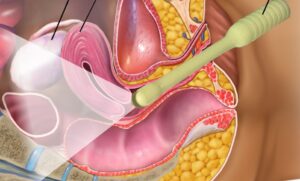

Λαπαροσκόπηση

Η λαπαροσκόπηση από γυναικολόγο είναι μια χειρουργική διαδικασία που χρησιμοποιεί τη λαπαροσκοπία για να εξετάσει ή να επέμβει σε προβλήματα που σχετίζονται με τον γυναικολογικό συνδυασμό, όπως οι όγκοι, οι κύστεις, οι εκδηλώσεις της εσωτερικής επιφάνειας της μήτρας (ενδομητρίωση), η εξασθένηση του κολπικού δακτυλίου, και άλλα προβλήματα.

Η διαδικασία πραγματοποιείται με τη χρήση ενός λαπαροσκοπίου, που είναι ένα εργαλείο που περιλαμβάνει μια φωτοκύτταρο και μια κάμερα, και εισάγεται μέσα στον κοιλιακό χώρο μέσω μιας μικρής τομής. Ο γυναικολόγος παρακολουθεί την εσωτερική επιφάνεια του κοιλιακού χώρου σε πραγματικό χρόνο σε μια οθόνη.

Οι πλεονεκτήματα της λαπαροσκοπίας συγκεκριμένα για γυναικολογικές επεμβάσεις περιλαμβάνουν:

- Ελάχιστος Επεμβατικός Χαρακτήρας: Οι τομές που απαιτούνται για τη λαπαροσκοπία είναι συνήθως πολύ μικρές σε σύγκριση με τις παραδοσιακές χειρουργικές επεμβάσεις.

- Σύντομος Χρόνος Ανάρρωσης: Οι γυναίκες που υποβάλλονται σε λαπαροσκοπία συνήθως έχουν σύντομους χρόνους ανάρρωσης σε σύγκριση με παραδοσιακές χειρουργικές επεμβάσεις.

- Λιγότερος Πόνος: Επειδή οι τομές είναι μικρές, ο πόνος μετά τη λαπαροσκοπία μπορεί να είναι λιγότερος σε σύγκριση με άλλες μεθόδους.

Οι γυναικολόγοι χρησιμοποιούν τη λαπαροσκοπία για ποικίλες επεμβάσεις, συμπεριλαμβανομένων της αφαίρεσης όγκων, της διόρθωσης της ενδομητρίωσης, της αφαίρεσης των όνεων, και άλλων επεμβάσεων που απαιτούν προσπέλαση στον γυναικολογικό χώρο.